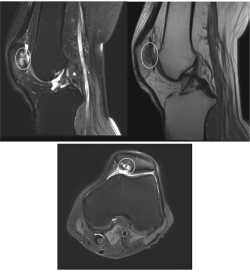

Radiographs, including anteroposterior, lateral, and sunrise views, were obtained and evident for a focal lucency of the posterior patella (see Figure 3). With this finding, it was recommended the patient to undergo MRI to confirm the presence of an OCD (see Figure 4), which was evident on that study.

Figure 4 - Click to enlarge in new windowFigure 4. Sagittal T2- and T1-weighted images as well as axial T2-weighted images (respectively). Ellipse about osteochondral defect with underlying bony edema.